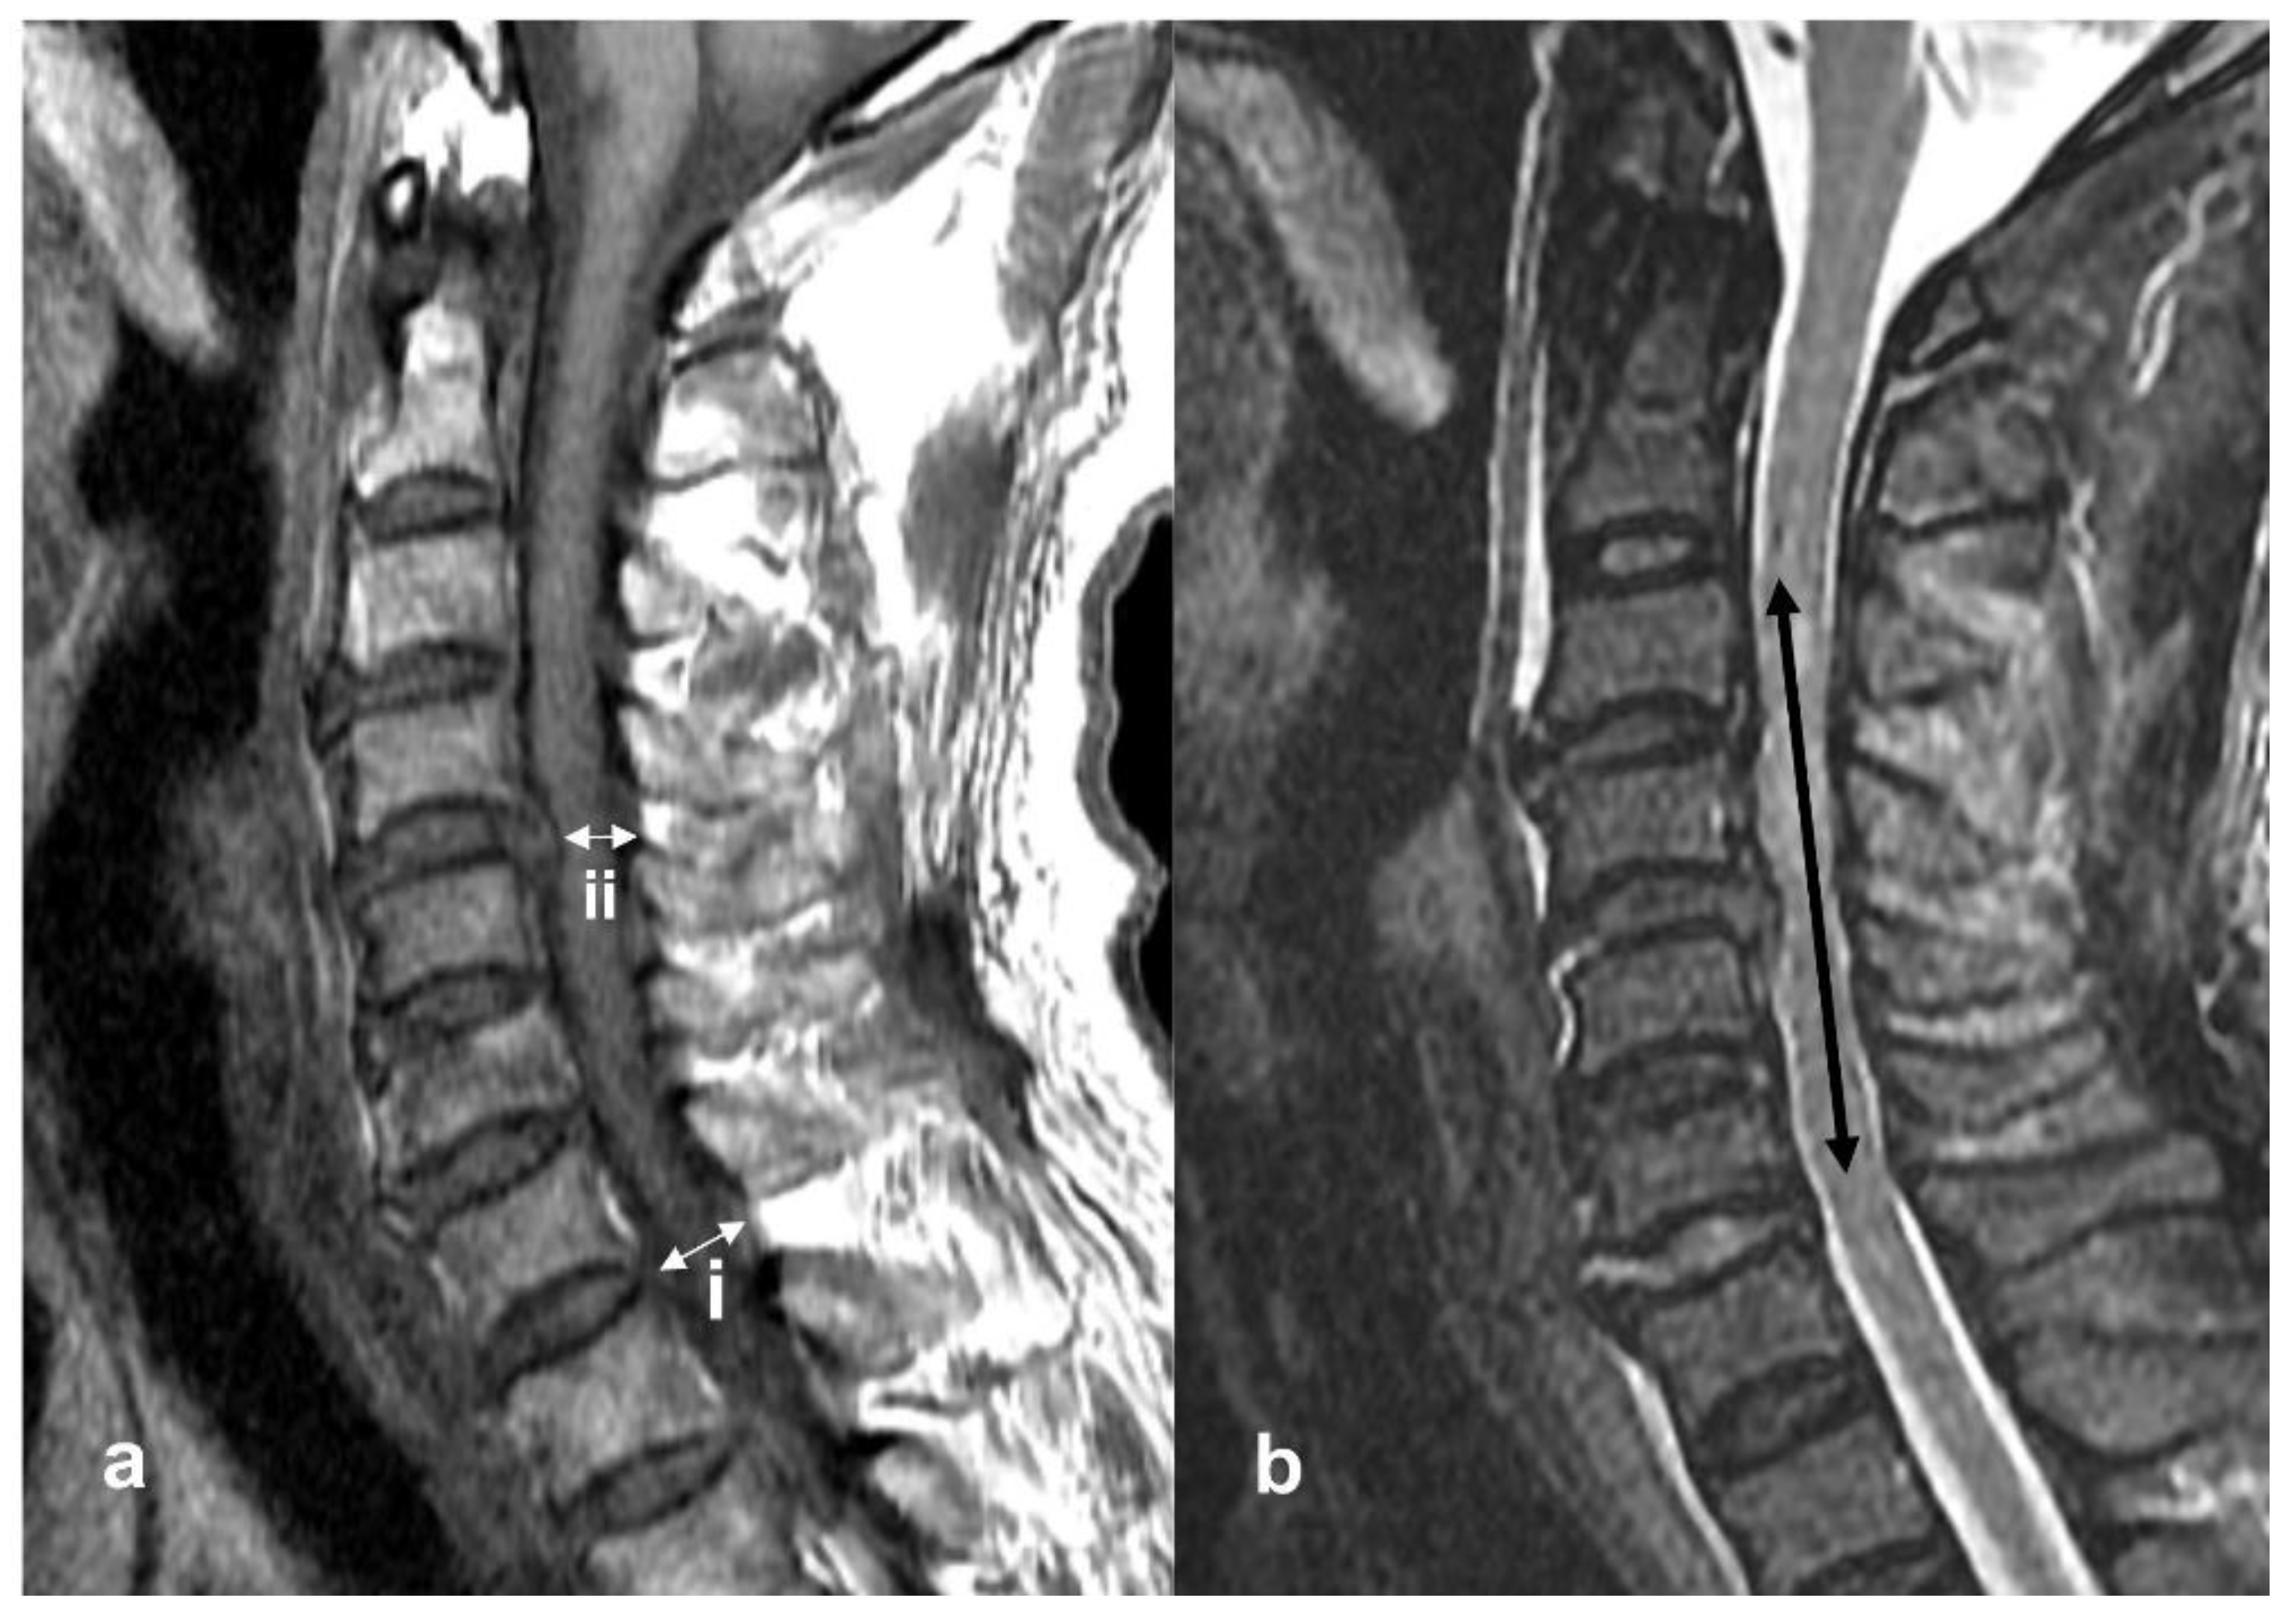

The rate of spinal cord compression was measured using sagittal view MRI (Figure 1a). The spinal cord diameter was measured at both the non-compressed level and the injured level on T1-weighted MRI images, and the compression rate was calculated using the following equation:

where (i) is the diameter of the cervical cord at the non-compression level and (ii) is the diameter of the cervical cord at the injured level [8].

(i − ii)/I × 100%

Sagittal magnetic resonance imagery (MRI) obtained in a 69-year-old man who presented with severe adult spinal cord injury without major bone injury and American Spinal Injury Association Impairment Scale (AIS) grade A. (a) T1-weighted image. (i) The diameter of the cervical cord at the non-compression level. (ii) The diameter of the cervical cord at the injured level. Compression rate was calculated by the equation. Compression rate was 35.2%. (b) T2-weighted image at C3-4-5-6 showed the signal change, and the rostrocaudal length of damage was measured in millimeters. Intramedullary lesion length (IMLL) was 62 mm.

Intramedullary lesion length (IMLL) was defined as the rostrocaudal length of high-signal intensity from the injury epicenter, measured in millimeters (Figure 1b). IMLL was measured on T2-weighted images [9].